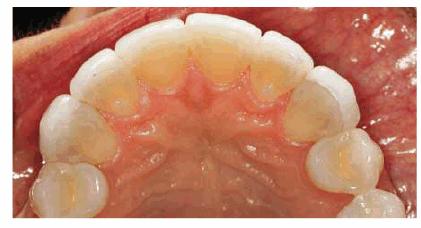

Figure 16-2A and B: Total neglect resulted in severe staining

of this patient's teeth.